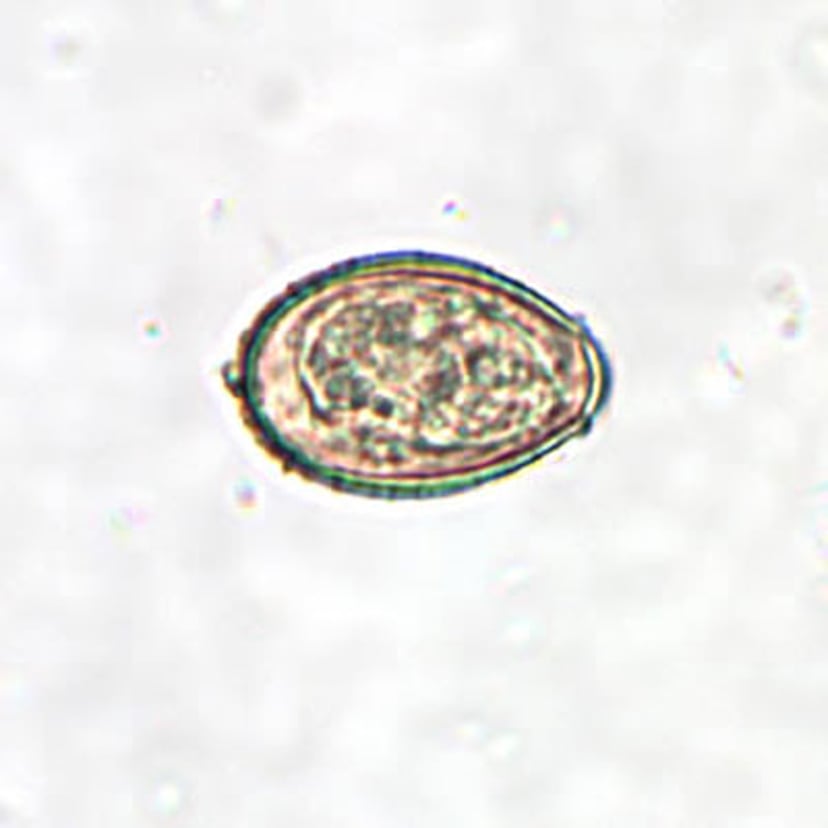

Clonorchis sinensis

(华支睾吸虫)卵

虫卵较小,尺寸范围为27至35微米乘以11至20微米。卵呈椭圆形,具有凸面的卵盖(保护性覆盖物或盖状结构),卵盖位于卵较小一端的可见的“肩部”上。放大倍数为400倍。